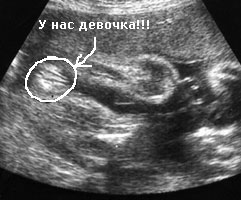

Kaip atrodo pilvukai per aštuonioliktą savaitę? Visiems skirtinga. Kai kurioms motinoms atrodė, kad jos praryja kamuolį, o kitoms pilvas driekėsi iš viršaus į apačią. Viskas gerai. Kartais jie net pagal savo pilvo formą bando atspėti, ar gims mergaitė, ar berniukas.Ir vis dėlto tik ultragarso specialistas gali jums užtikrintai pasakyti, ar šią savaitę jums paskirtas toks tyrimas, ir vaikas nori pasidalyti paslaptimi.

Ultragarsinės nuotraukos